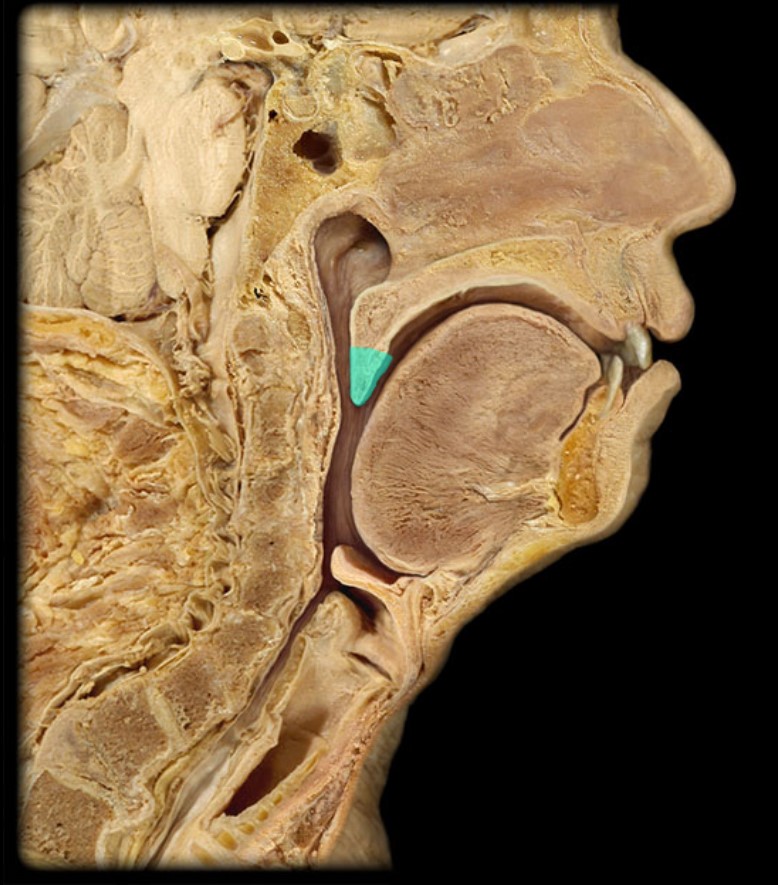

Anatomy 5 - Bifurcated Skull

29 Terms

Pharyngeal Tonsil

21

New cards

Auditory Hiatus

22

New cards

Torus Tubarius

23

New cards

Sphenoid Sinus

24

New cards

Inferior Nasal Concha

25

New cards

Middle Nasal Concha

26

New cards

Superior Nasal Concha

27

New cards

Nasal Vestibule

28

New cards

External Nares

29

New cards

Frontal Sinus